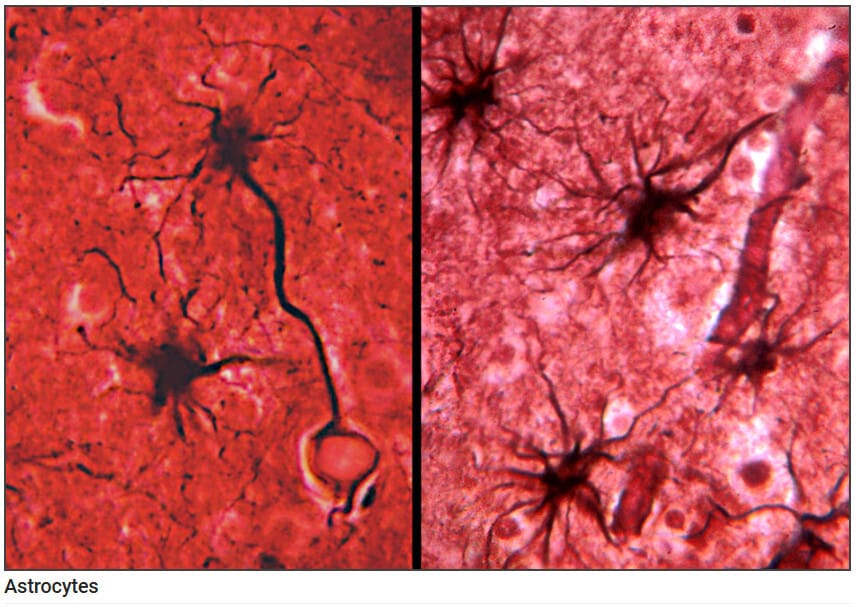

성상세포 (Astrocytes)

Blood Brain Barrier, 신경세포에 영양소 공급, 신경전달물질 조절

성상세포는 별 모양의 돌기가 뻗은 형태이며, 뉴런과 모세혈관 모두에 접촉할 수 있습니다. 이 세포는 혈액-뇌 장벽(BBB)을 유지하고, 세포외 칼륨 농도 조절, 신경전달물질 흡수, 손상 시 흉터(glial scar) 형성 등을 통해 신경계 환경을 안정화합니다.

| 성상세포 , 별아교 세포 (Astrocytes) |

| 🟧 혈관과 뉴런 사이에서 이온 농도와 대사를 조절하며, 뇌의 항상성을 유지하는 데 핵심적인 역할을 합니다. |